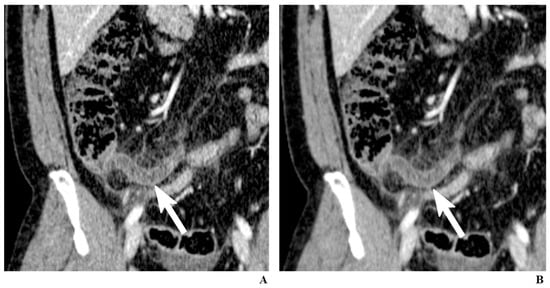

2.7. Iterative Reconstruction

Figure 1. A 34-year-old man with appendicitis. Contrast-enhanced coronal CT images reconstructed by filtered back-projection (FBP) (A) and iterative reconstruction (IR) (B). While both images clearly depict an inflamed appendix (arrows), the image reconstructed using IR generates less noise, which can alleviate the practitioners’ reluctance to low-dose CT.